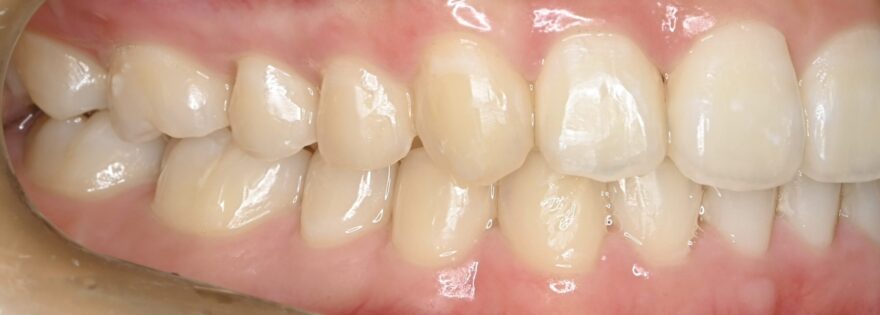

治療後の口腔内写真

約2年の動的期間(歯を動かす時期)で、ここまで整った歯並びになりました。

インビザラインでもワイヤー矯正でも、最終的な仕上がりに差はありません。

八重歯が完全に治りました。

前歯には後戻りを防止するための保定装置を装着しています。

下顎の前歯にもワイヤーによる保定装置を装着しています。